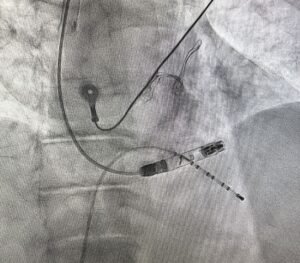

First Successful Aveir VR Implantation via Right Jugular Access After Failed Femoral Approach

Today, we successfully performed our first implantation of the Aveir VR device via right jugular access.In our center, among the…